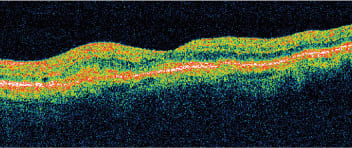

Preferential hyperacuity perimetry showed an abnormality (Figure 1), and conversion to CNV was confirmed by OCT (Figure 2) and IVFA (Figure 3). Fundus photography (Figure 4) showed an area of hemorrhage nasal to the fovea, but no obvious subretinal fluid or subretinal exudate. Using PHP, we were able to rule out vision impairment due to cataracts and our retina specialist started treatment for wet AMD. After treatment with bevacizumab (Avastin, Genentech), triamcinolone acetonide and bevacizumab again, each one month apart, the patient's metamorphopsia in the left eye resolved. If her CNV had gone undetected any longer, it is likely she would not have had such a successful outcome.

Figure 2. OCT shows an area of elevation localized to the retinal pigment epithelium.